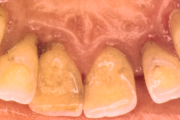

Krooniline parodontiit

Krooniline parodontiit on mikroobide poolt põhjustatud hammaste tugikudede põletik, mille tulemusena tekib progresseeruv alveolaarluu (nähtav röntgenograamil) ja periodontaalligamendi destruktsioon, igemetaskute moodustumine, igeme retsessioon või mõlemad kahjustused kombineeritult. Loe edasi »

- igemepiir on taandunud (3)

- luu destruktsioon (5)

- puudulik suuhügieen (5)

- igemepealne hambakivi (5)